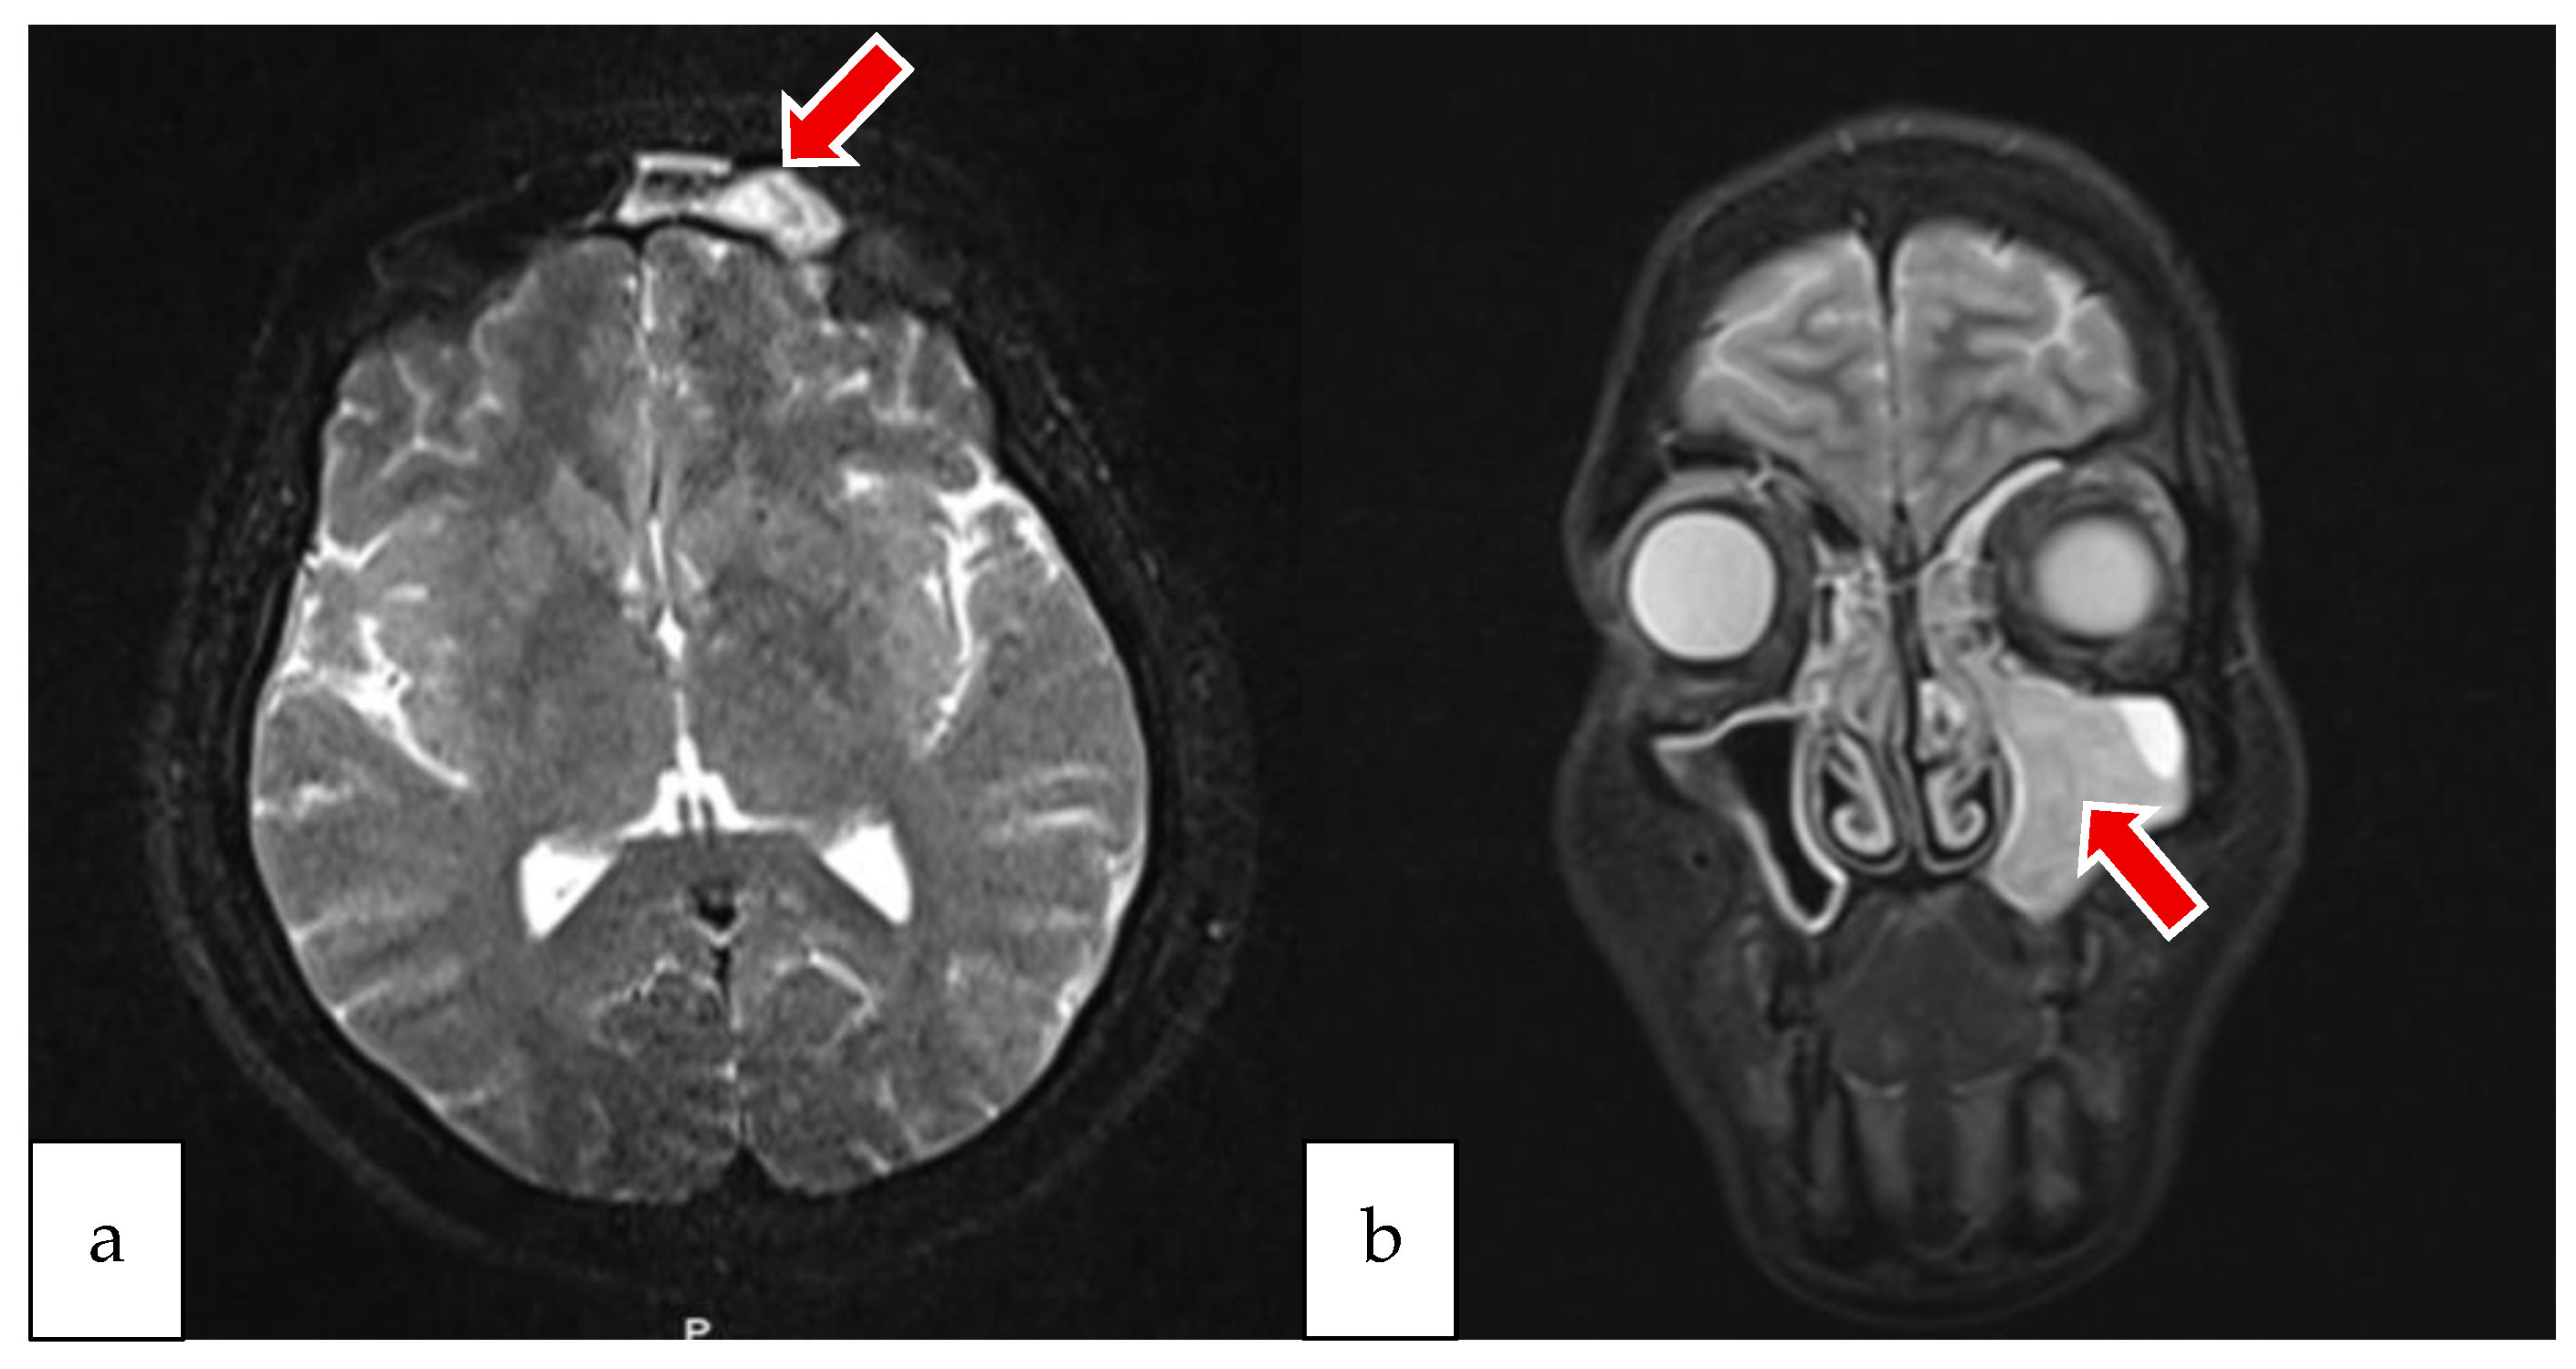

2.1. Case 1

2.2. Case 2